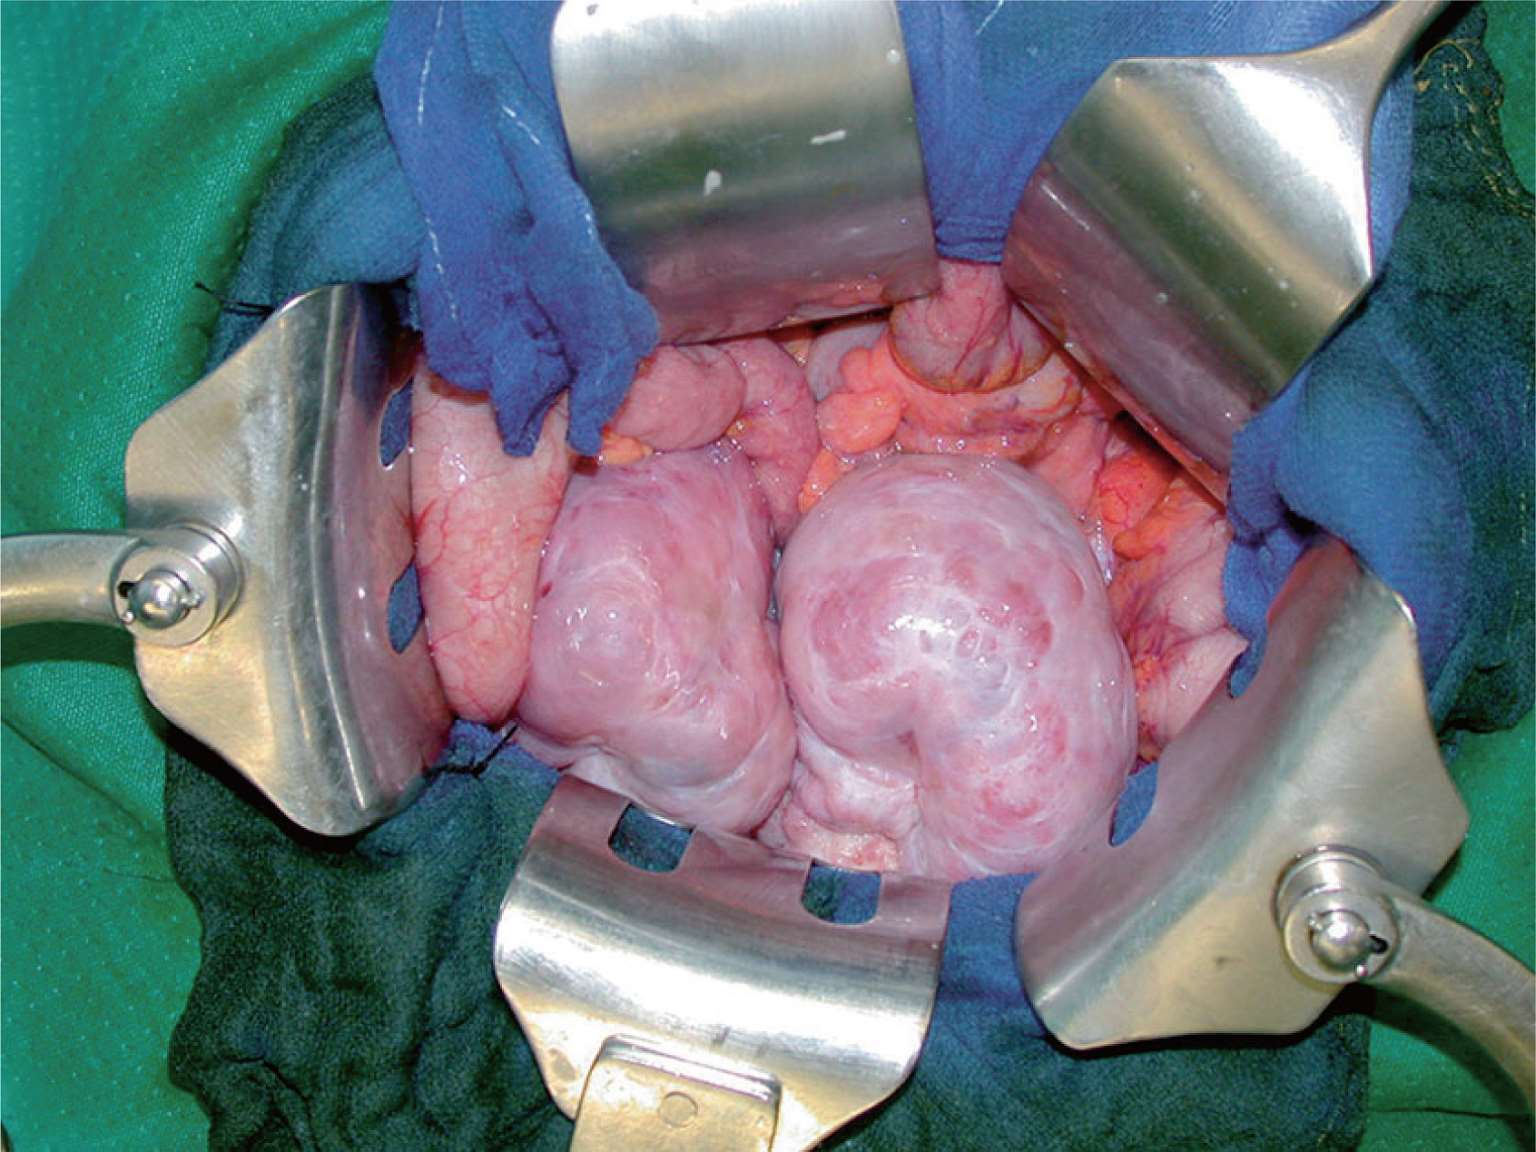

图2-10 在横结肠系膜上、下间隙中探查有无腹膜癌结节。

图2-11 小肠及小肠系膜癌结节。